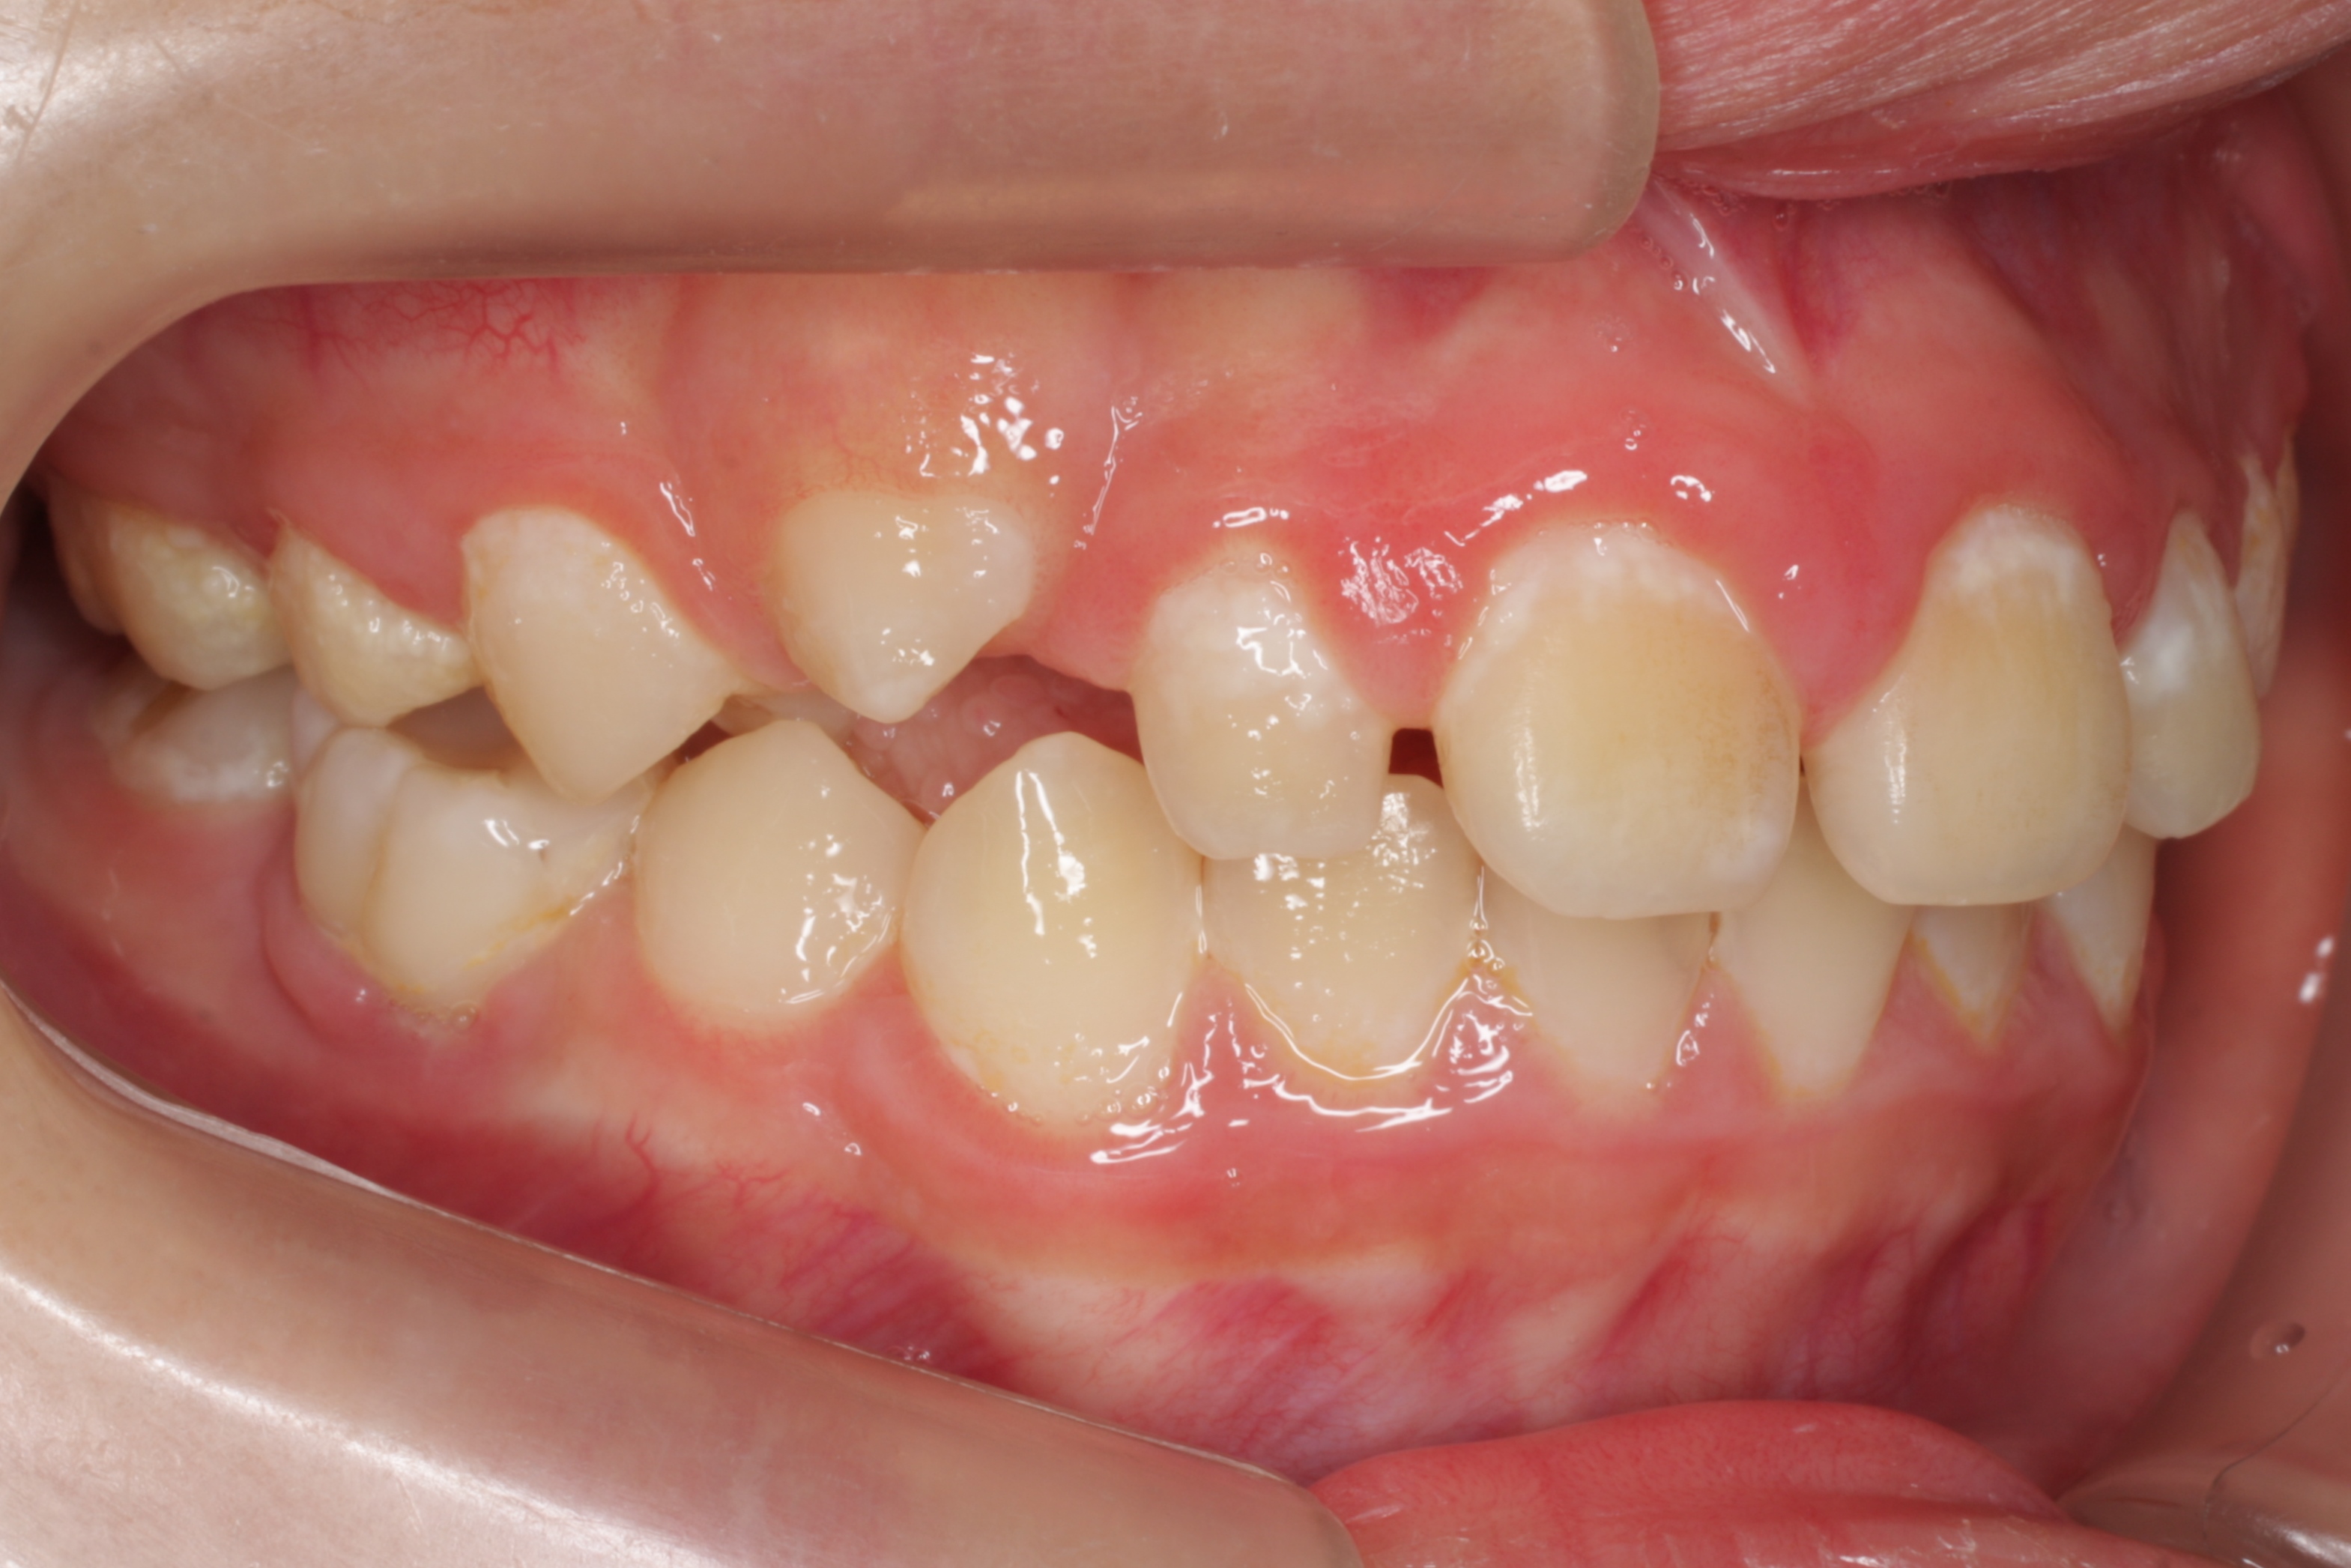

学校健診で虫歯と言われ、来院してくれた子供さんです。とても良い子で、お家の方も感じの良い方です。ただ、気がつくチャンスが無かっただけなのです。歯の大切さと予防歯科の重要性に。

歯科医や学校がもっと予防歯科の普及に頑張らないといけないなと深く反省させられる瞬間です。ごめんなさい。ごめんなさい。

一般的には「何本か虫歯があるので、歯医者に行ってなおしてもらおう」といった感覚なのでしょう。悲しいかな日本ではそれがフツーです。

問題はこの子の家庭に予防歯科の概念と知識が欠如している事なのです。何回も言っているように歯医者に行っても歯は元通りにはなりませんし、修繕が追いつかない程の速度で虫歯ができています。

この子は、これから一生の間に少なくとも100回は歯ぐきに注射をされて、少なくとも300回は通院し、歯を削られたり、神経を抜かれたり、銀歯を入れられたり、そしていつかは歯を抜かれたりするようになります。歯科医師の私にはこの悲しい将来が見えてしまいます。

一日も早く、一人でも多くの方が予防歯科の重要性に気がついて欲しいと思います。そのために私達歯科医療従事者も頑張ります!